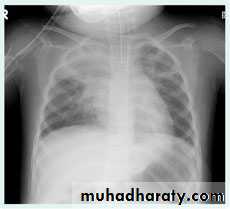

Right upper lobe collapse has distinctive features, and is usually easily identified on frontal chest radiographs .

Radiographic features

Chest radiograph

Collapse of the right upper lobe is usually relatively easy to identify on frontal radiographs. Features consist of :

increased density in the upper medial aspect of the right hemithorax

elevation of the horizontal fissure

loss of the normal right medial cardiomediastinal contour

elevation of the right hilum

hyperinflation of the right middle and lower lobe result in increased translucency of the mid and lower parts of the right lung

right juxtaphrenic peak

A common cause of lobar collapse is a hilar mass. When a right hilar mass is combined with collapse of the right upper lobe, the result is an S shape to elevated horizontal fissure. This is known as Golden S sign .

Non-specific signs indicating right sided atelectasis are also usually present including:

elevation of the hemidiaphragm

crowding of the right sided ribs

shift of the mediastinum and trachea to the right